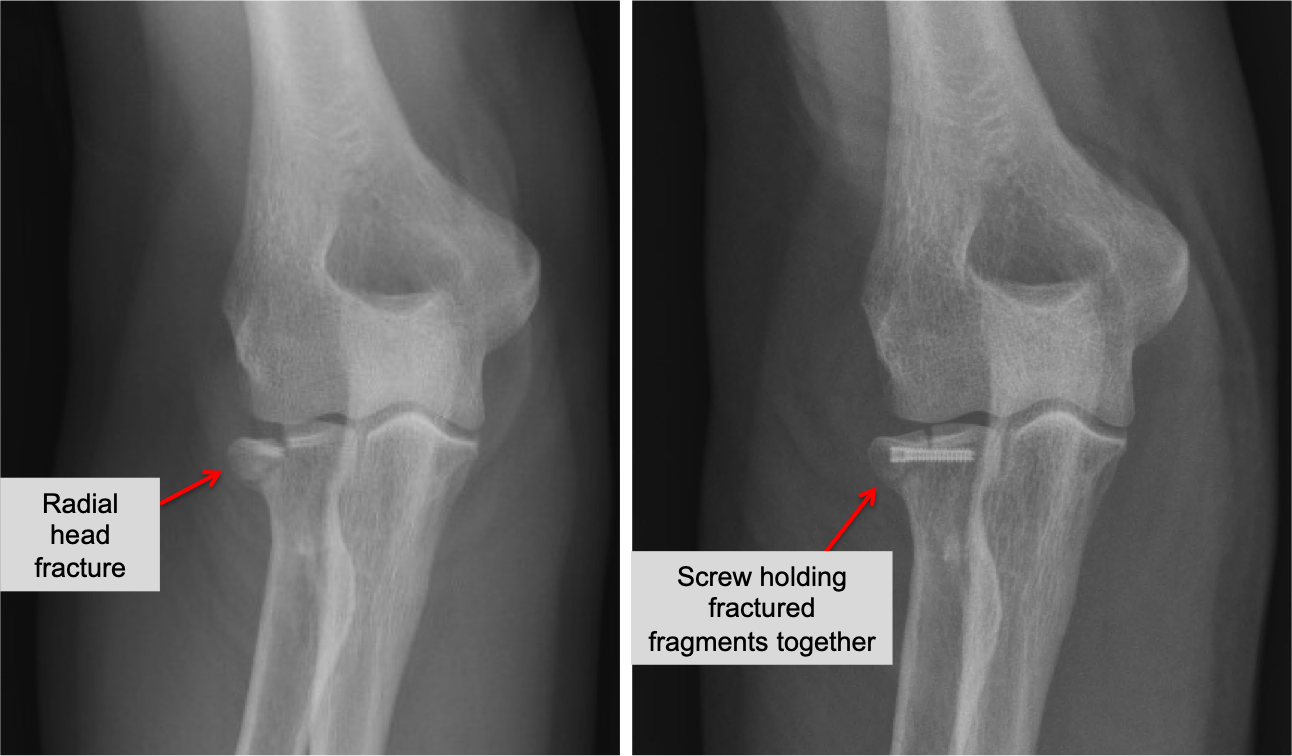

Closed fracture

Closed fracture 113 фотографий